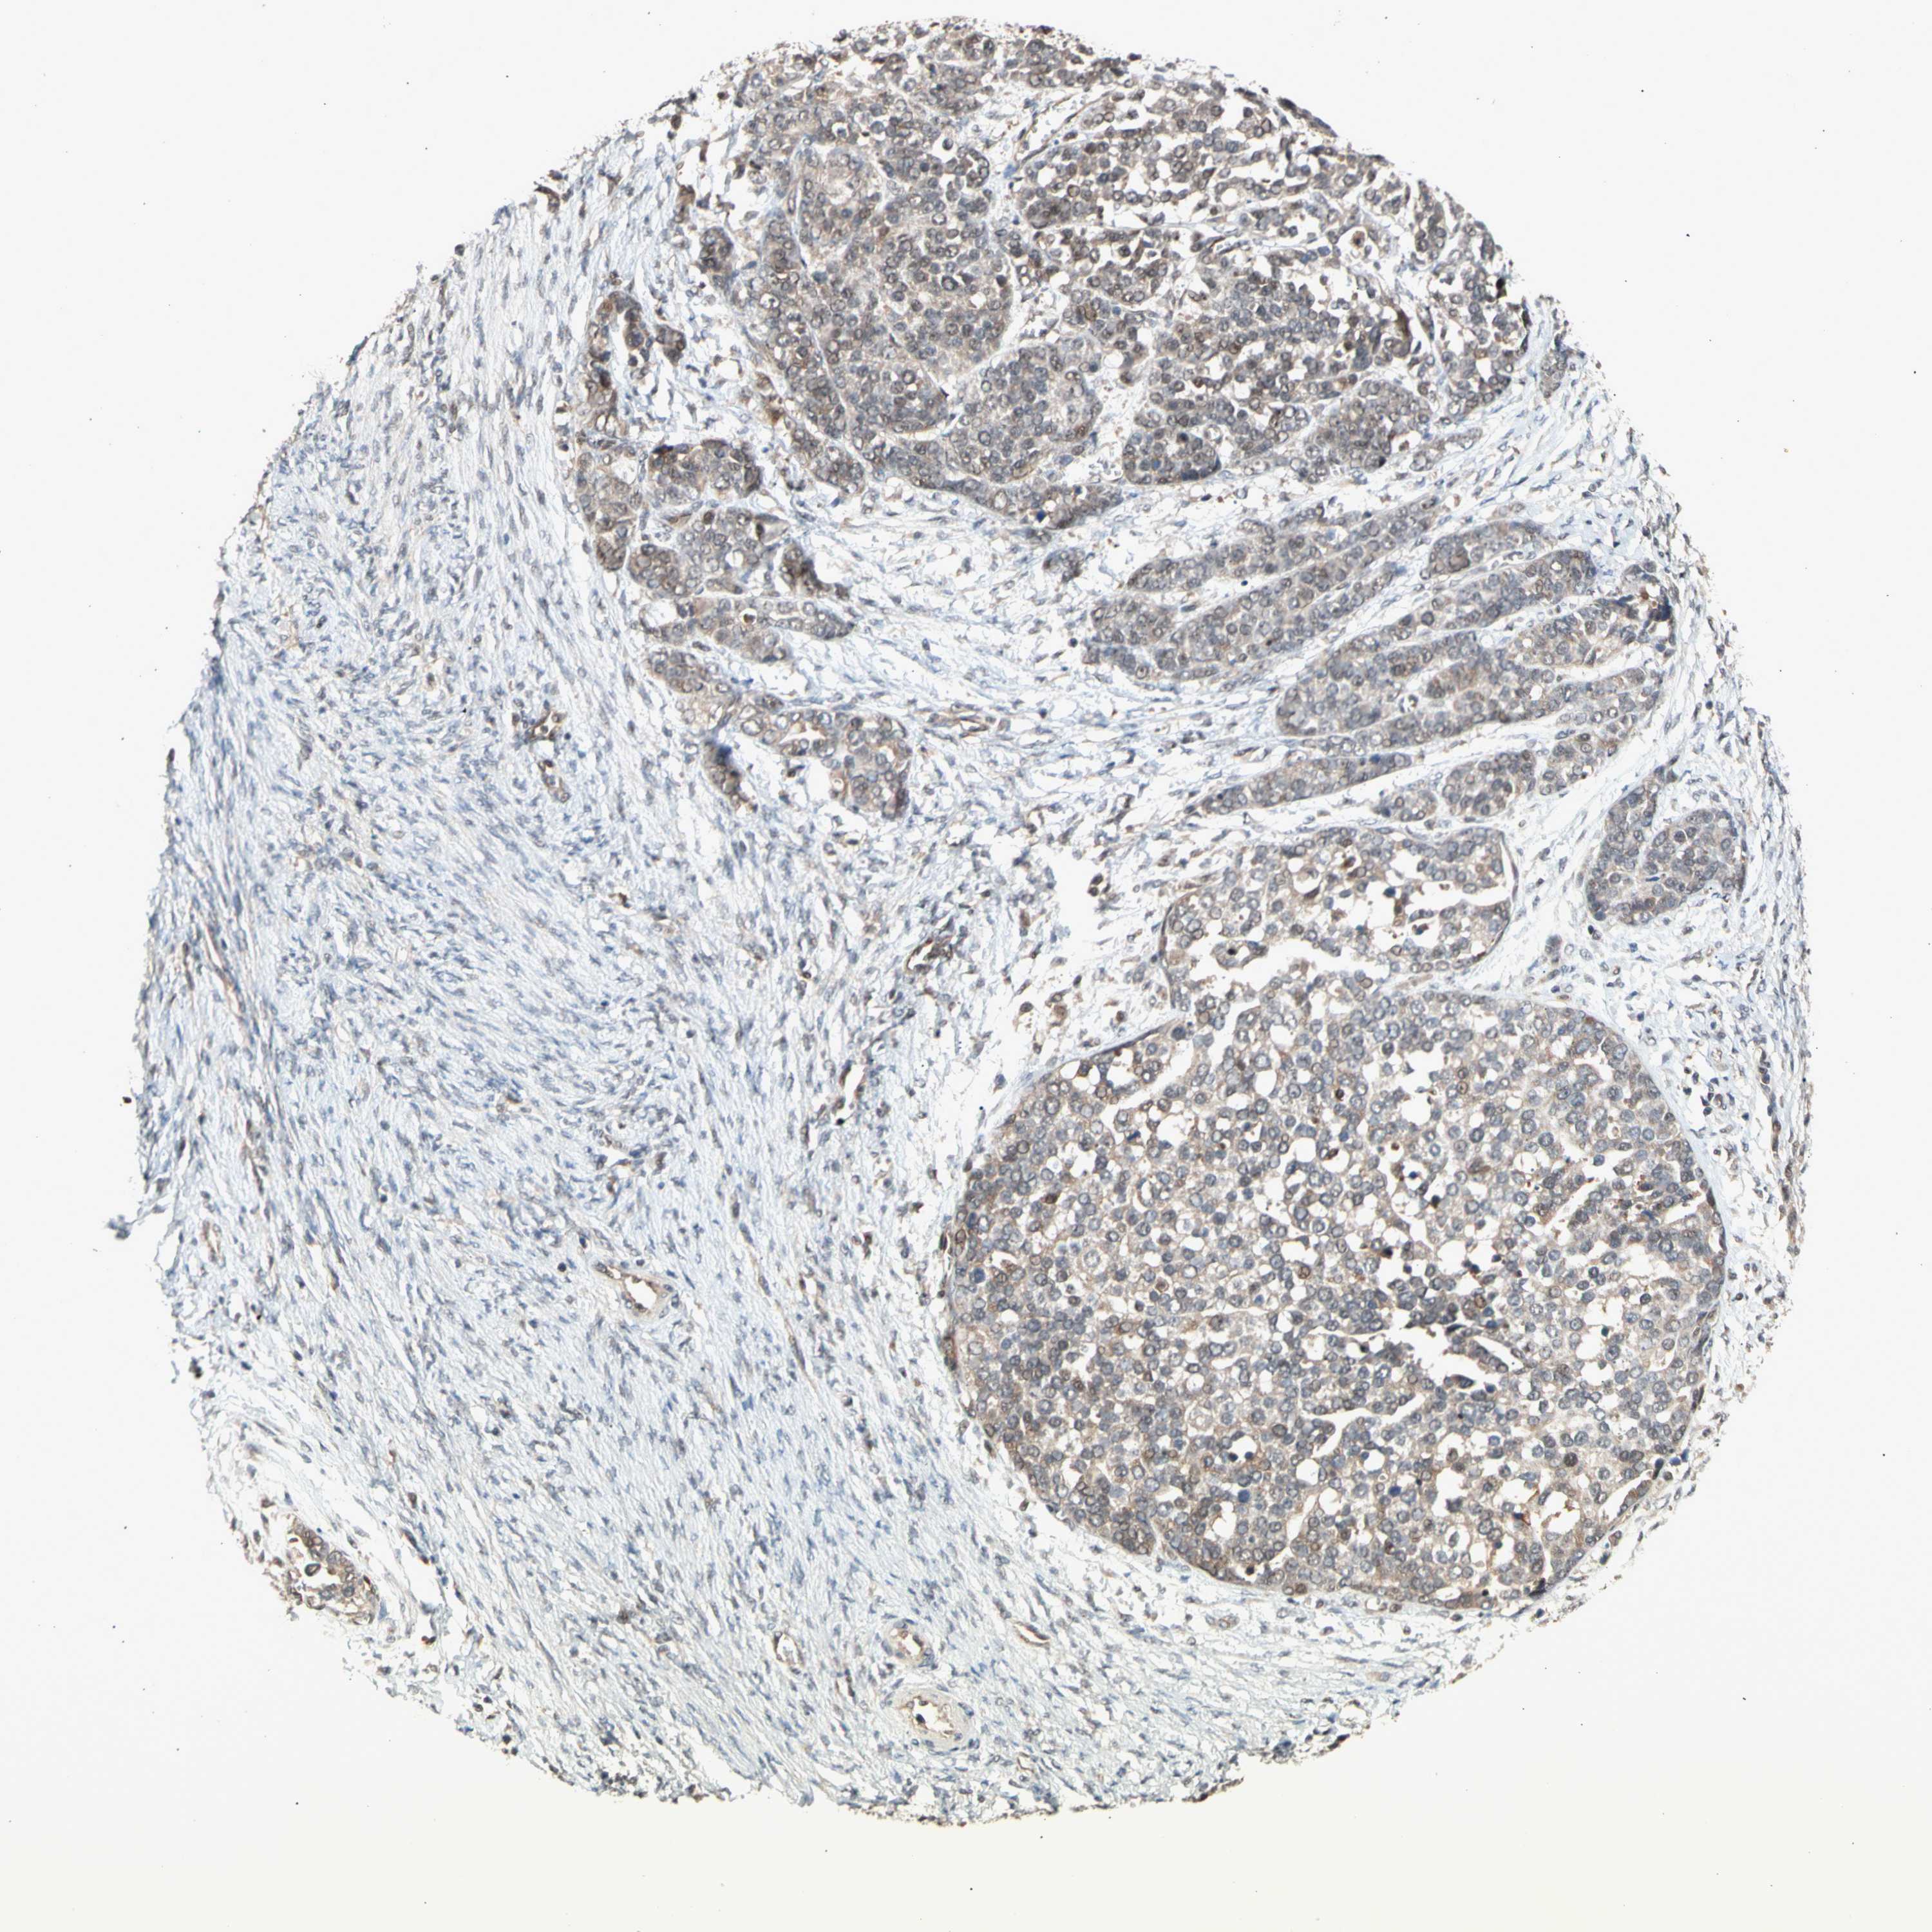

OVARIAN CANCER - Protein expressioni

A mouse-over function shows sample information and annotation data. Click on an image to view it in a full screen mode. Samples can be filtered based on level of antibody staining by selecting one or several of the following categories: high, medium, low and not detected. The assay and annotation is described here.

Note that samples used for immunohistochemistry by the Human Protein Atlas do not correspond to samples in the TCGA dataset.

Antibody stainingi

Antibody staining in the annotated cell types in the current human tissue is reported as not detected, low, medium, or high, based on conventional immunohistochemistry profiling in selected tissues. This score is based on the combination of the staining intensity and fraction of stained cells.

Each image is clickable and will lead to virtual microscopy that enables deeper exploration of all samples and also displays staining intensity scores, fraction scores and subcellular localization as well as patient and tissue information for each sample.

Antibody HPA008160

Staining

High

Medium

Low

Not detected

Intensity

Strong

Moderate

Weak

Negative

Quantity

>75%

75%-25%

<25%

None

Location

Nuclear

Cytoplasmic/membranous

Cytoplasmic/membranous,nuclear

Cystadenocarcinoma, serous, NOS

Carcinoma, endometroid

Cystadenocarcinoma, mucinous, NOS

Carcinoma, NOS